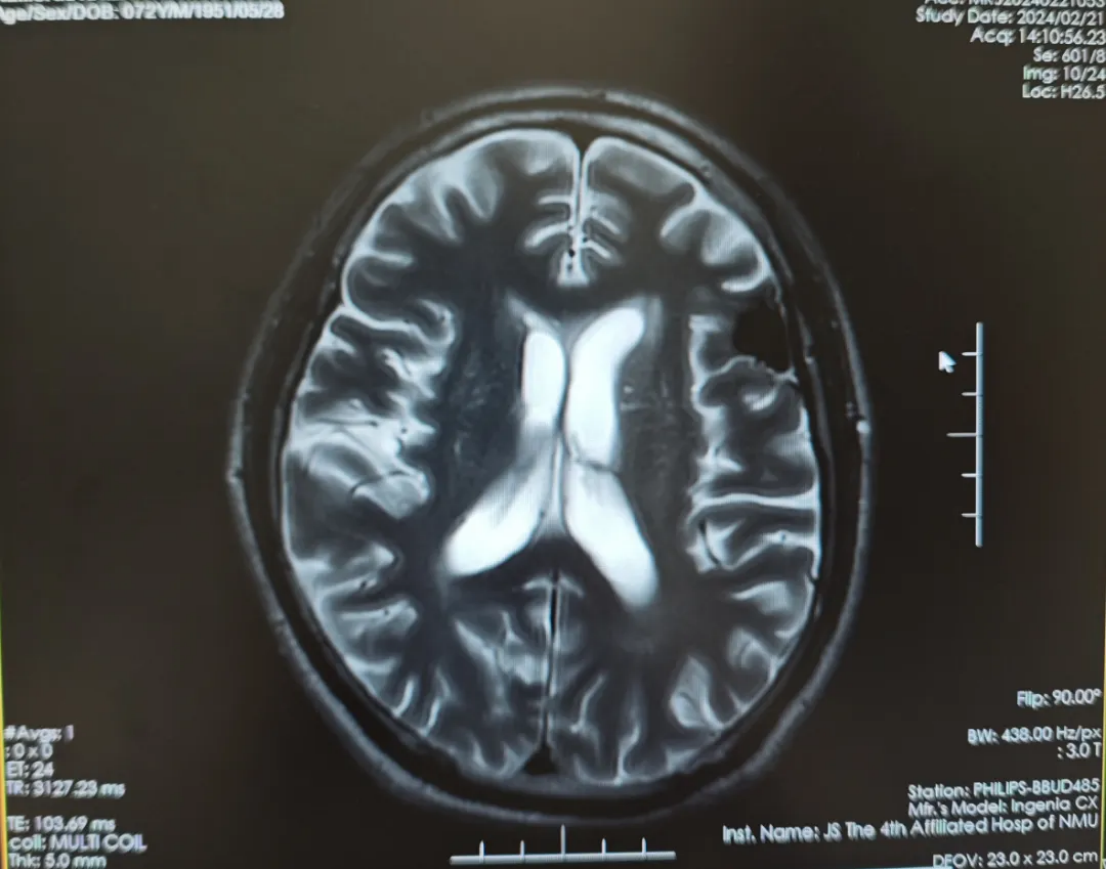

2024-02-21第一次随访,复查头颅磁共振平扫提示:左侧额叶转移瘤治疗后复查,局部软化灶形成,较前片(2023-12-15)相仿;两侧额叶及放射冠区少许缺血灶;老年性脑改变(图4)。

图4 第一次随访复查头颅磁共振平扫